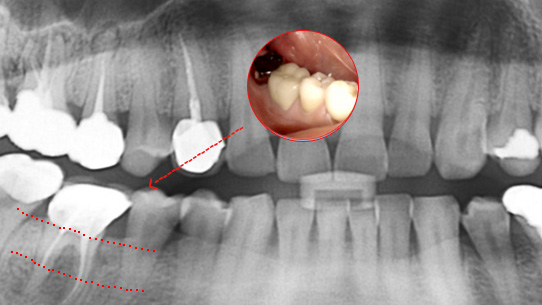

치아 뿌리 주변 염증과 치조골이 녹아내려 통증과 더불어 치아가 흔들리는 상태로 내원한 환자입니다. 우선 큐렛으로 잇몸 속 치석을 제거하였습니다.

뿌리 주변 염증은 신경관을 소독하고 약재를 삽입하는 신경치료를 시행하였습니다.

치근단 염증

신경관 소독

신경관 약재 삽입

약재 주입 후 반응